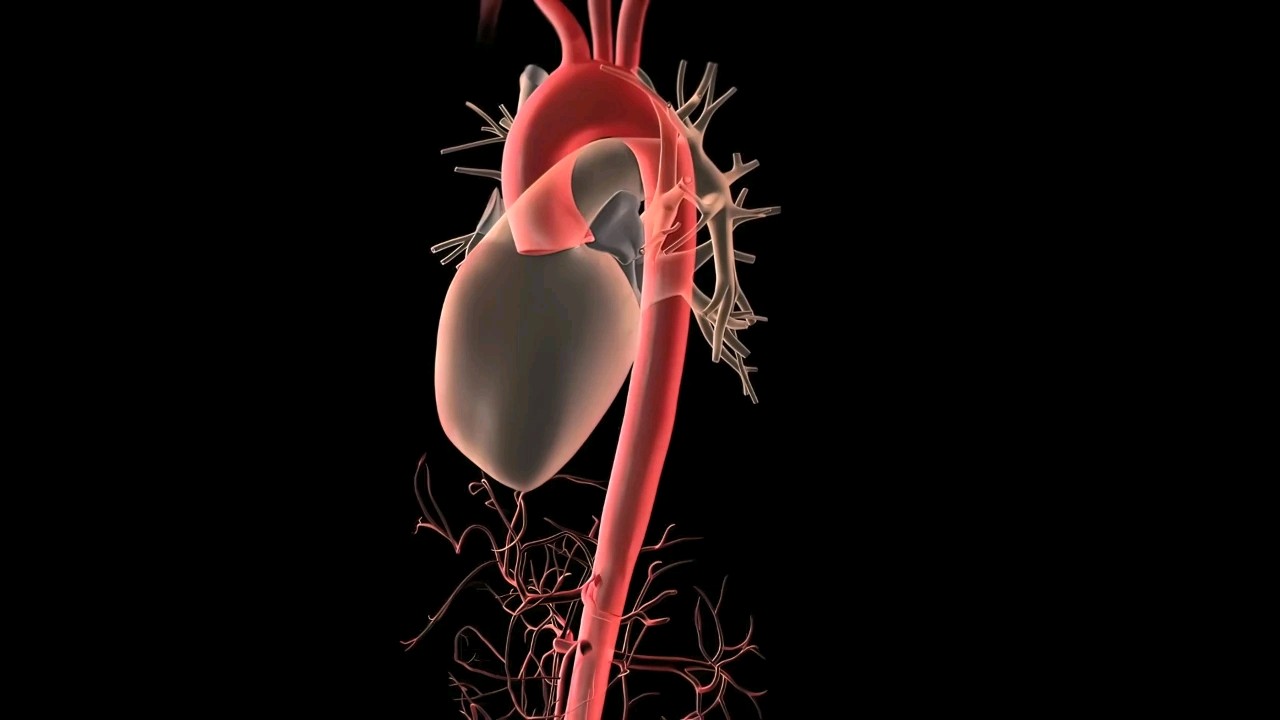

这得从主动脉的功能说起。它之所以能承担大量输血的任务,是因为有层厚厚的弹性纤维能以强大的弹性,随心脏舒缩提供血流动力。但随着年龄增长,这些纤维也会老化,血管也变得“脆皮”。如果这时还遭到动脉硬化、高血压、病菌感染等打击纤维会加速老化,让血管壁越来越薄。血管难以承载没日没夜的血液通过,只好被迫扩张膨大,以容纳更多血液,久而久之就胀成瘤样血包一旦瘤体过于庞大(直径≥5cm),脆弱的血管壁受不住压力就可能发生破裂。麻烦的地方就在于在这个早期形成过程中,很多人没有明显症状,等到瘤体扩大到一定程度,感到疼痛才警觉起来。而持续性隐隐作痛,甚至疼痛突然加剧,像被撕裂一样,就说明瘤体有破裂征兆,需要即刻就医。此外,还有一些人会摸到搏动性肿块,随着心脏有节奏地微微颤动,也要及时检查。

高血压高血压意味着血液流动对血管造成异常高的压力。这会使主动脉长期处于应激状态,渐渐就受损变薄,甚至撕开一道裂口。当动脉血涌进裂口时就形成主动脉瘤的一种:主动脉夹层动脉瘤。另外,高压血流的冲刷本身也是加快动脉硬化形成,促进主动脉瘤破裂的重要原因。烟瘾不断如果你以为吸烟只伤肺,那就太天真了!尼古丁会通过肺部血液循环进入心脏,再从心脏向动脉冲刺。既刺激血管内细胞增生,堵塞血管,还诱发炎症,损害弹性纤维,增加主动脉瘤风险。有关研究表明:吸烟者发生腹主动脉瘤的风险是非吸烟者的5.23倍。病菌感染大多是因梅毒感染。